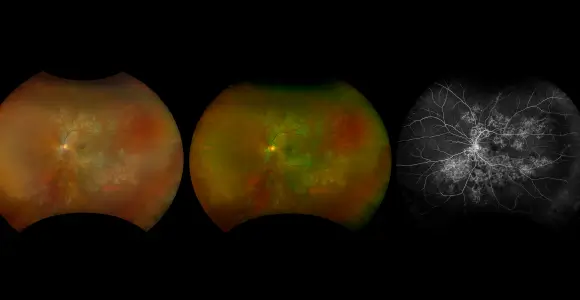

optomap Multimodal Uveitic Disease Cases

Optos offers multimodal imaging with all ultra-widefield devices. Having both ultra-widefield and four images captured in less than one second has been shown to enhance pathology detection and disease management as well as improve practice and clinic flow. Ultra-widefield multimodal imaging is important across all access points of patient care - screening, detection, diagnosis, and treatment.